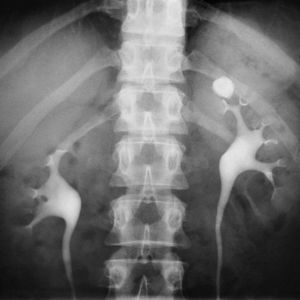

This material contains content which some users might find distrubingX-Ray examination showing kidney stone in the Left kidney

The major calyx, renal pyramids, and ureters are well seen by using a contract medium administered intravenously.